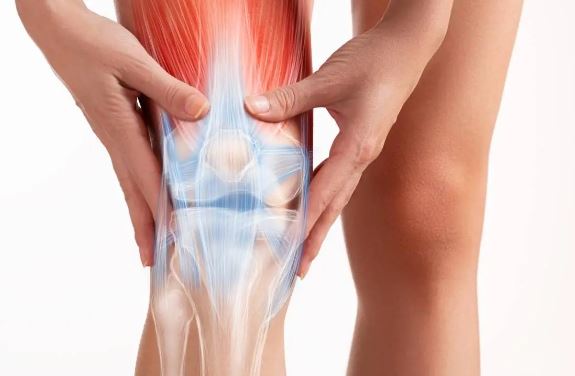

दुर्बिणीद्वारे सांध्याची शस्त्रक्रिया (ऑथर्थोस्कोपी)

अर्थ्रोस्कोपी ही एक शस्त्रक्रिया आहे जी सांध्यांच्या समस्यांचे निदान आणि उपचार करण्यासाठी वापरली जाते. एका छोट्या छिद्राद्वारे सांध्यात एक लहान कॅमेरा (अर्थ्रोस्कोप) टाकला जातो, ज्यामुळे डॉक्टरांना सांध्याची स्थिती पाहता येते, निदान करता येते, आणि कधी-कधी खराब झालेले लिगामेंट्स आणि सांध्याच्या सूजेसारख्या स्थितींचे उपचार करता येतात, मोठ्या कापाशिवाय.